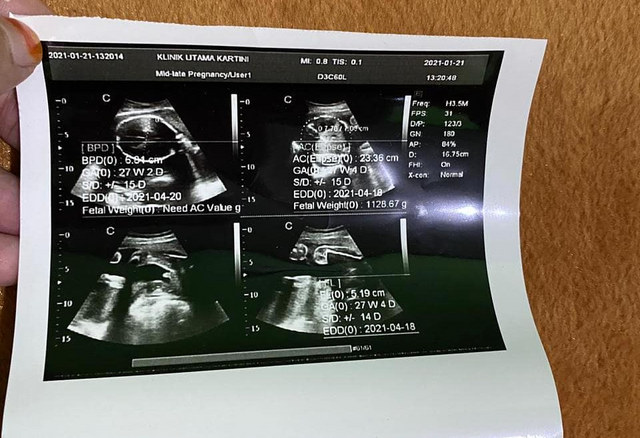

Usg 4 Dimensi Penjelasan Hasil Usg Trimester 2 Dan 3 Seperti Pada Postingan Saya Sebelumnya Hasil Usg Dalam Bentuk Gambar Yang Di Print Ada Beberapa Keterangan Di Dalamnya Keterangan Pada Gambar

Usg 4 Dimensi Penjelasan Hasil Usg Trimester 2 Dan 3 Seperti Pada Postingan Saya Sebelumnya Hasil Usg Dalam Bentuk Gambar Yang Di Print Ada Beberapa Keterangan Di Dalamnya Keterangan Pada Gambar

Usg 4 Dimensi Penjelasan Hasil Usg Trimester 2 Dan 3 Seperti Pada Postingan Saya Sebelumnya Hasil Usg Dalam Bentuk Gambar Yang Di Print Ada Beberapa Keterangan Di Dalamnya Keterangan Pada Gambar

Usg 4 Dimensi Penjelasan Hasil Usg Trimester 2 Dan 3 Seperti Pada Postingan Saya Sebelumnya Hasil Usg Dalam Bentuk Gambar Yang Di Print Ada Beberapa Keterangan Di Dalamnya Keterangan Pada Gambar